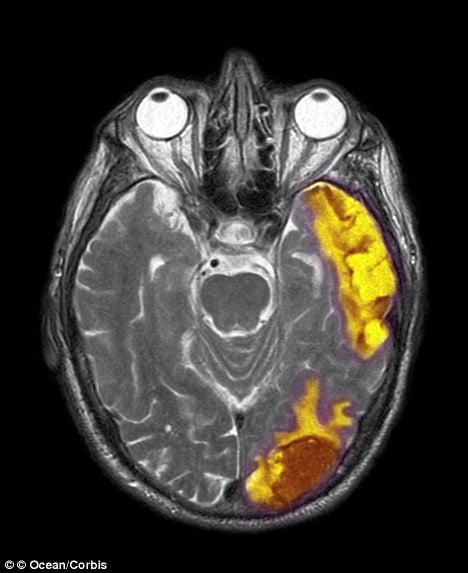

Pesquisadores descobriram áreas do cérebro responsáveis ??pelas crenças e experiências espirituais.

Há muito que se teorizou que um "ponto Deus" existe no cérebro e agora parece que não pode realmente ser mais do que um.

"Nós encontramos uma base neuropsicológica para a espiritualidade, mas não está isolado em uma área específica do cérebro", disse o professor de psicologia Johnstone.

"Algumas partes do cérebro desempenham mais funções predominantes, mas todas trabalham juntas para facilitar as experiências dos indivíduos espirituais".

Os pesquisadores da Universidade de Missouri chegaram a conclusão que a espiritualidade é um fenômeno complexo e que várias áreas do cérebro são responsáveis ??por muitos aspectos de experiências espirituais.